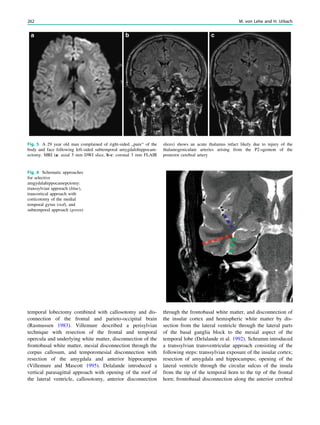

Fig. 1 An 8-year old girl presented with two focal motor seizures and

postictal left arm paralysis. MRI shows superior sagittal sinus

thrombosis (a–c, arrows) with two small hemorrhages at the gray

matter–white matter junction in the right frontal lobe (a, hollow

arrows)